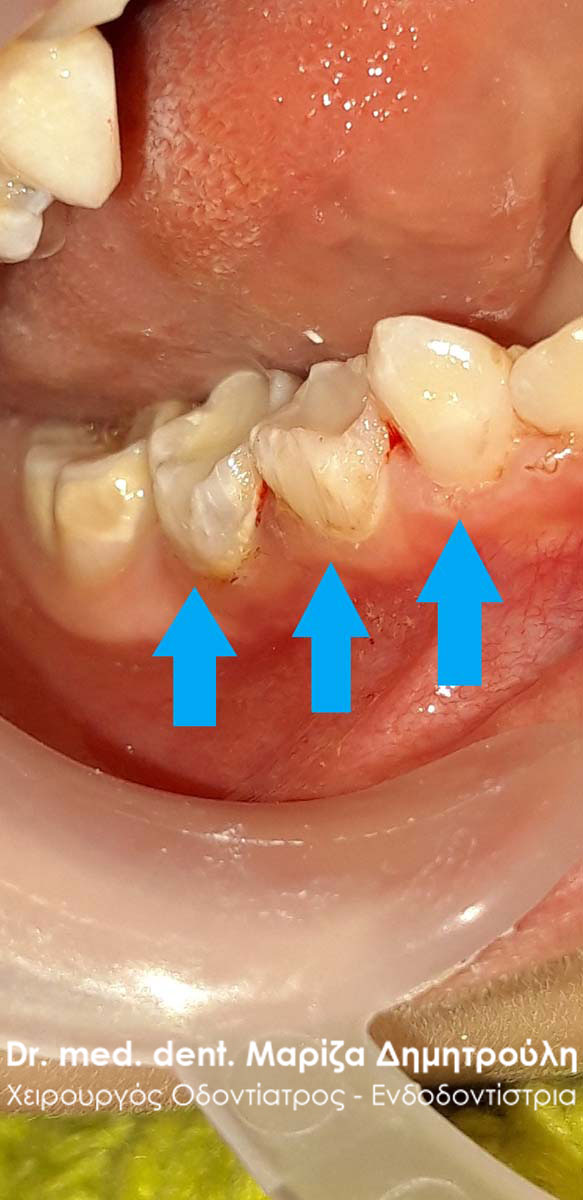

Περιστατικό – Αυχενικό σφράγισμα δοντιού

Σκοπός της ασθενούς ήταν τόσο η αισθητική όσο και η λειτουργική (η αθενής είχε ευαισθησία στα ψυχρά ροφήματα και τροφές) αποκατάσταση των αυχενικών αλλοίωσεων στους κάτω δεξιούς προγομφίους. Η αποκατάσταση πραγματοποιήθηκε με λευκά σφραγίσματα σύνθετης ρητίνης.

ΠΡΙΝ

META